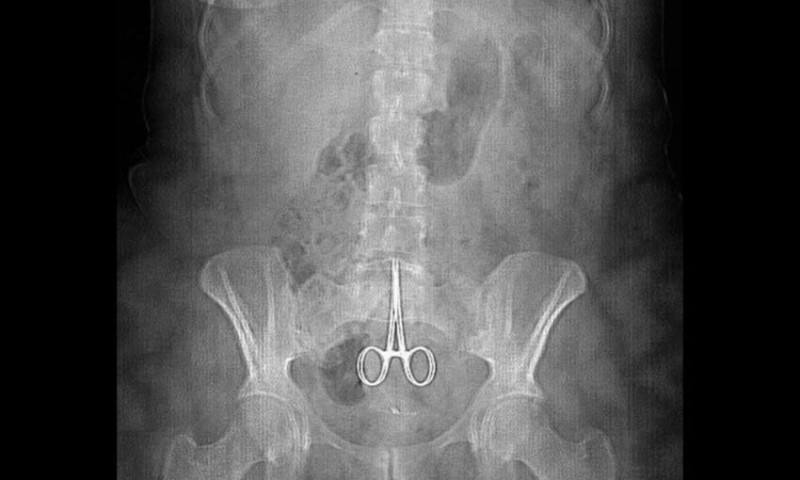

हनोइ (भियतनाम), २० पुस । शल्यक्रियाका क्रममा चिकित्सकको लापरवाहीका कारण १८ वर्ष अघि एकजनाको पेटमा छुटेको कैँची निकालिएको छ ।

समाचार एजेन्सीहरुका अनुसार भियनतामका ५४ वर्षीय मा भान न्हाटको पेटबाट चिकित्सकले शल्यक्रिया गरी कैंची निकालेका हुन् । उनको पेटमा १८ वर्षअघि शल्यक्रियाकै क्रममा चिकित्सकले भूलवस कैंची छाडेका थिए ।

शल्यक्रियापछि उनको पेटबाट १५ सेन्टीमिटर लामो कैंची निकालिएको हो । त्यसअघि पेटमा कैंची रहे पनि उनको स्वास्थ्यमा कुनै समस्या नदेखिएको बताइएको छ ।

उत्तरी भियतनामको थाइ नुभेन प्रान्तका ती पुरुष हालै एउटा दुर्घटनाको शिकार भएका थिए । घाइते अवस्थामा उपचारका लागि अस्पताल लगिएका उनको अल्ट्रासाउन्ड गर्दा चिकित्सकले पेटमा कुनै धारिलो बस्तु रहेको पत्ता लगाएपछि शल्यक्रिया गरिएको थियो ।

स्थानीय संचारमाध्यमका अनुसार सन् १९९८ मा पहिलोपटक उनको शल्यक्रिया भएको थियो । उक्त कैंची त्यतिबेला नै चिकित्सकले भूलवस उनको पेटमै छाडेको बताइएको छ ।

भियतनामको स्वास्थ्य मन्त्रालयले सम्बन्धित अस्पताललाई एक साताभित्र ती व्यक्तिको पेटमा कैंची कसले छोडेको हो भन्नेबारे प्रतिवेदन पेश गर्न आदेश दिएको छ ।